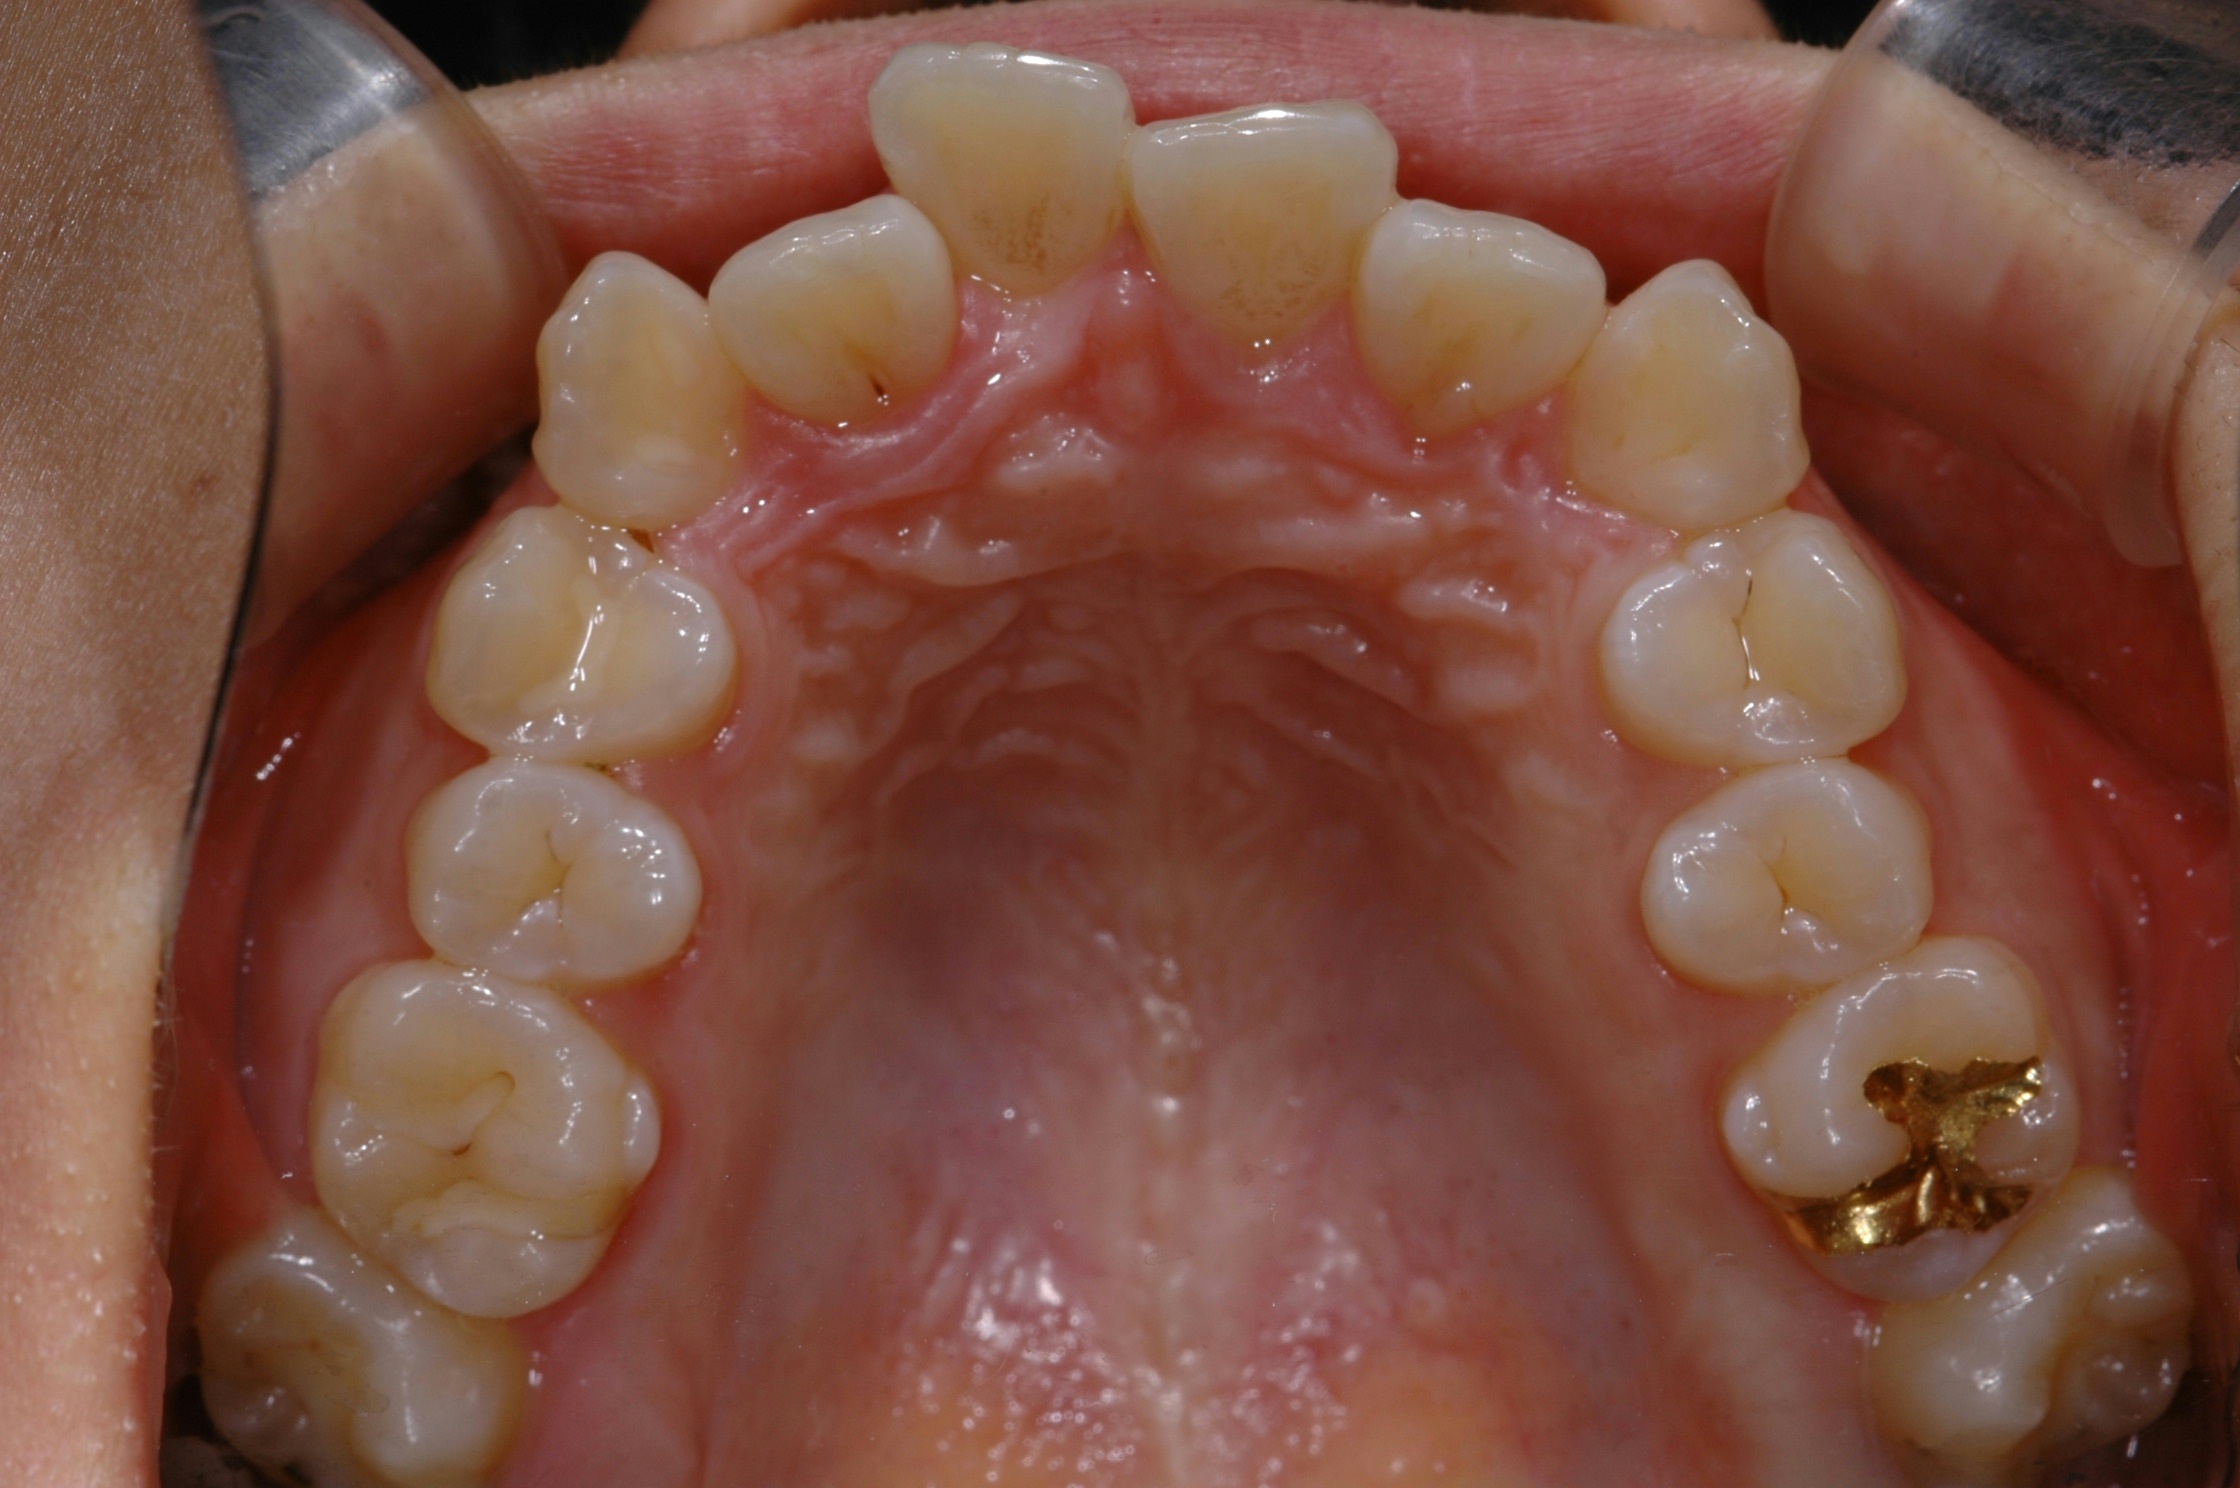

치료 전 사진입니다.